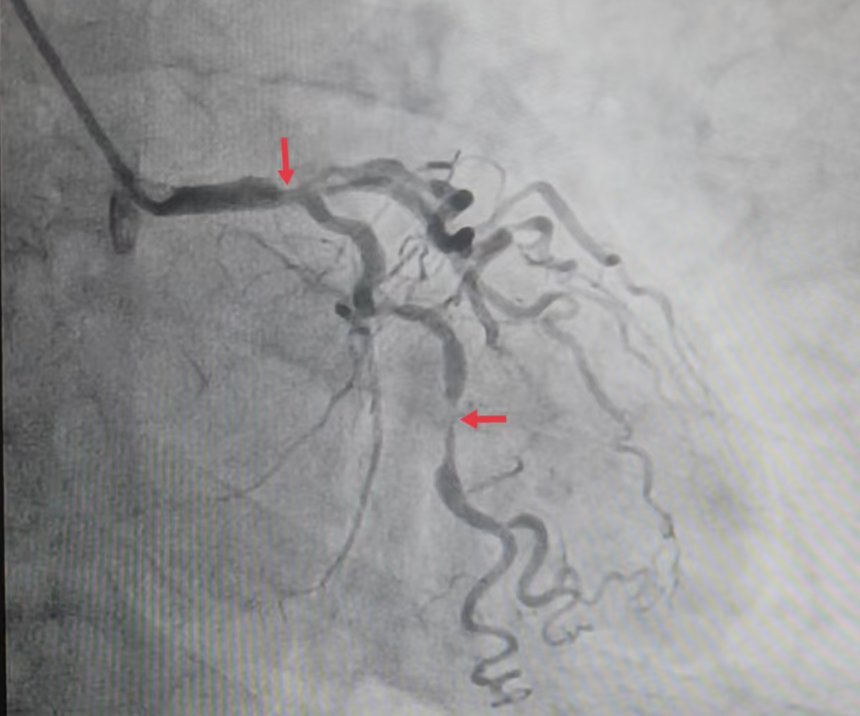

▲冠状动脉造影提示:左主干末端-左前降支近段80%节段性狭窄,左回旋支中段80%节段性狭窄

术前的患者,正被层层健康难题困住:冠脉造影显示多支血管病变且条件极差,心脏供血如同“堵塞的管道”,随时可能中断;间断发作的心绞痛,让他稍一活动就胸口发闷、冷汗直冒,连日常起身都需小心翼翼;叠加的焦虑症与甲状腺功能减退,更让身体调节能力雪上加霜,情绪时常陷入低落,对治疗充满顾虑。